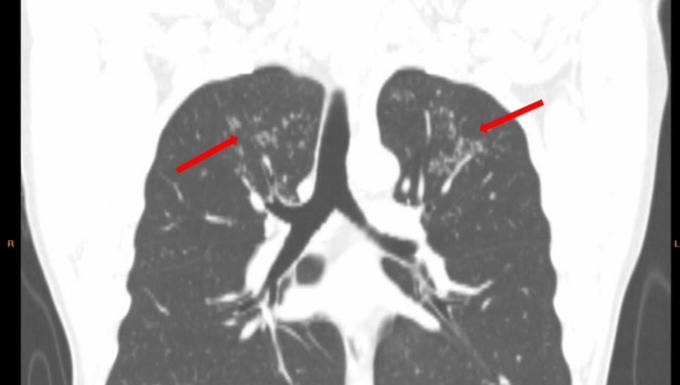

Hình ảnh tổn thương dạng nụ trên cành ở thùy trên hai phổi bệnh nhân. Ảnh: Bệnh viện cung cấp

Ngày 6/12,BS.CK2 Cao Thị Hồng,Phó khoa Chăm sóc sức khỏe theo yêu cầu,phụ trách Trung tâm kiểm tra sức khỏe Chợ Rẫy Việt - Nhật (HECI),cho biết CT ngực liều thấp phát hiện có hình ảnh tổn thương ở thùy trên phổi. Tầm soát chuyên sâu về lao cho kết quả dương tính. Bệnh nhân được điều trị theo phác đồ bệnh lao khoảng 3 tháng nay,không còn triệu chứng ớn lạnh nhẹ về chiều.